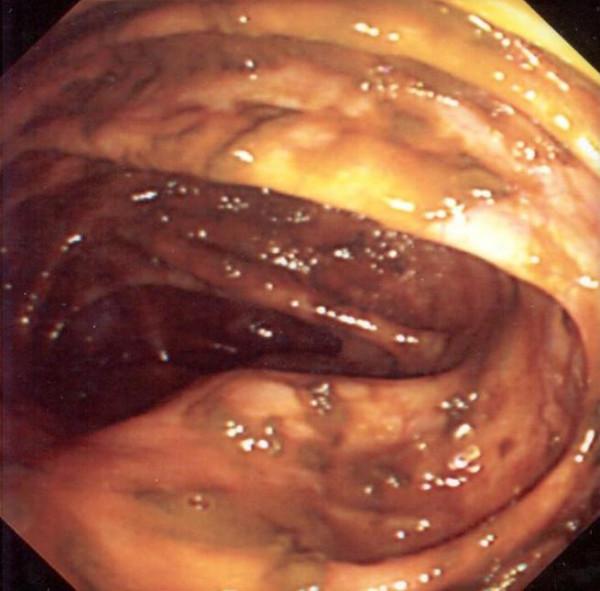

We report a case of appendicular adenocarcinoma found unexpectedly in a 43 year old male who presented with urinary symptoms. Cystoscopy and uretero-renoscopy showed normal bladder but external compression of the ureters and therefore bilateral stents were inserted. CT scan showed a caecal mass. After colonoscopy, that showed external compression, and diagnostic laparoscopy the patient underwent right hemicolectomy. Histopathology revealed well differentiated adenocarcinoma with signet ring morphology with multiple lymph node involvement. The patient was referred for chemotherapy where he received infusional 5 fluorouracil but died 7 months after surgery.

我们报告一例43岁男性患者,因出现泌尿系统症状意外发现阑尾腺癌。膀胱镜检查和输尿管肾镜检查显示膀胱正常,但输尿管受到外部压迫,因此插入了双侧支架。CT扫描显示盲肠有肿块。结肠镜检查显示外部压迫,经诊断性腹腔镜检查后,患者接受了右半结肠切除术。组织病理学显示为高分化腺癌,伴有印戒样形态,并有多个淋巴结受累。患者被转诊接受化疗,接受了静脉输注5-氟尿嘧啶治疗,但术后7个月死亡。